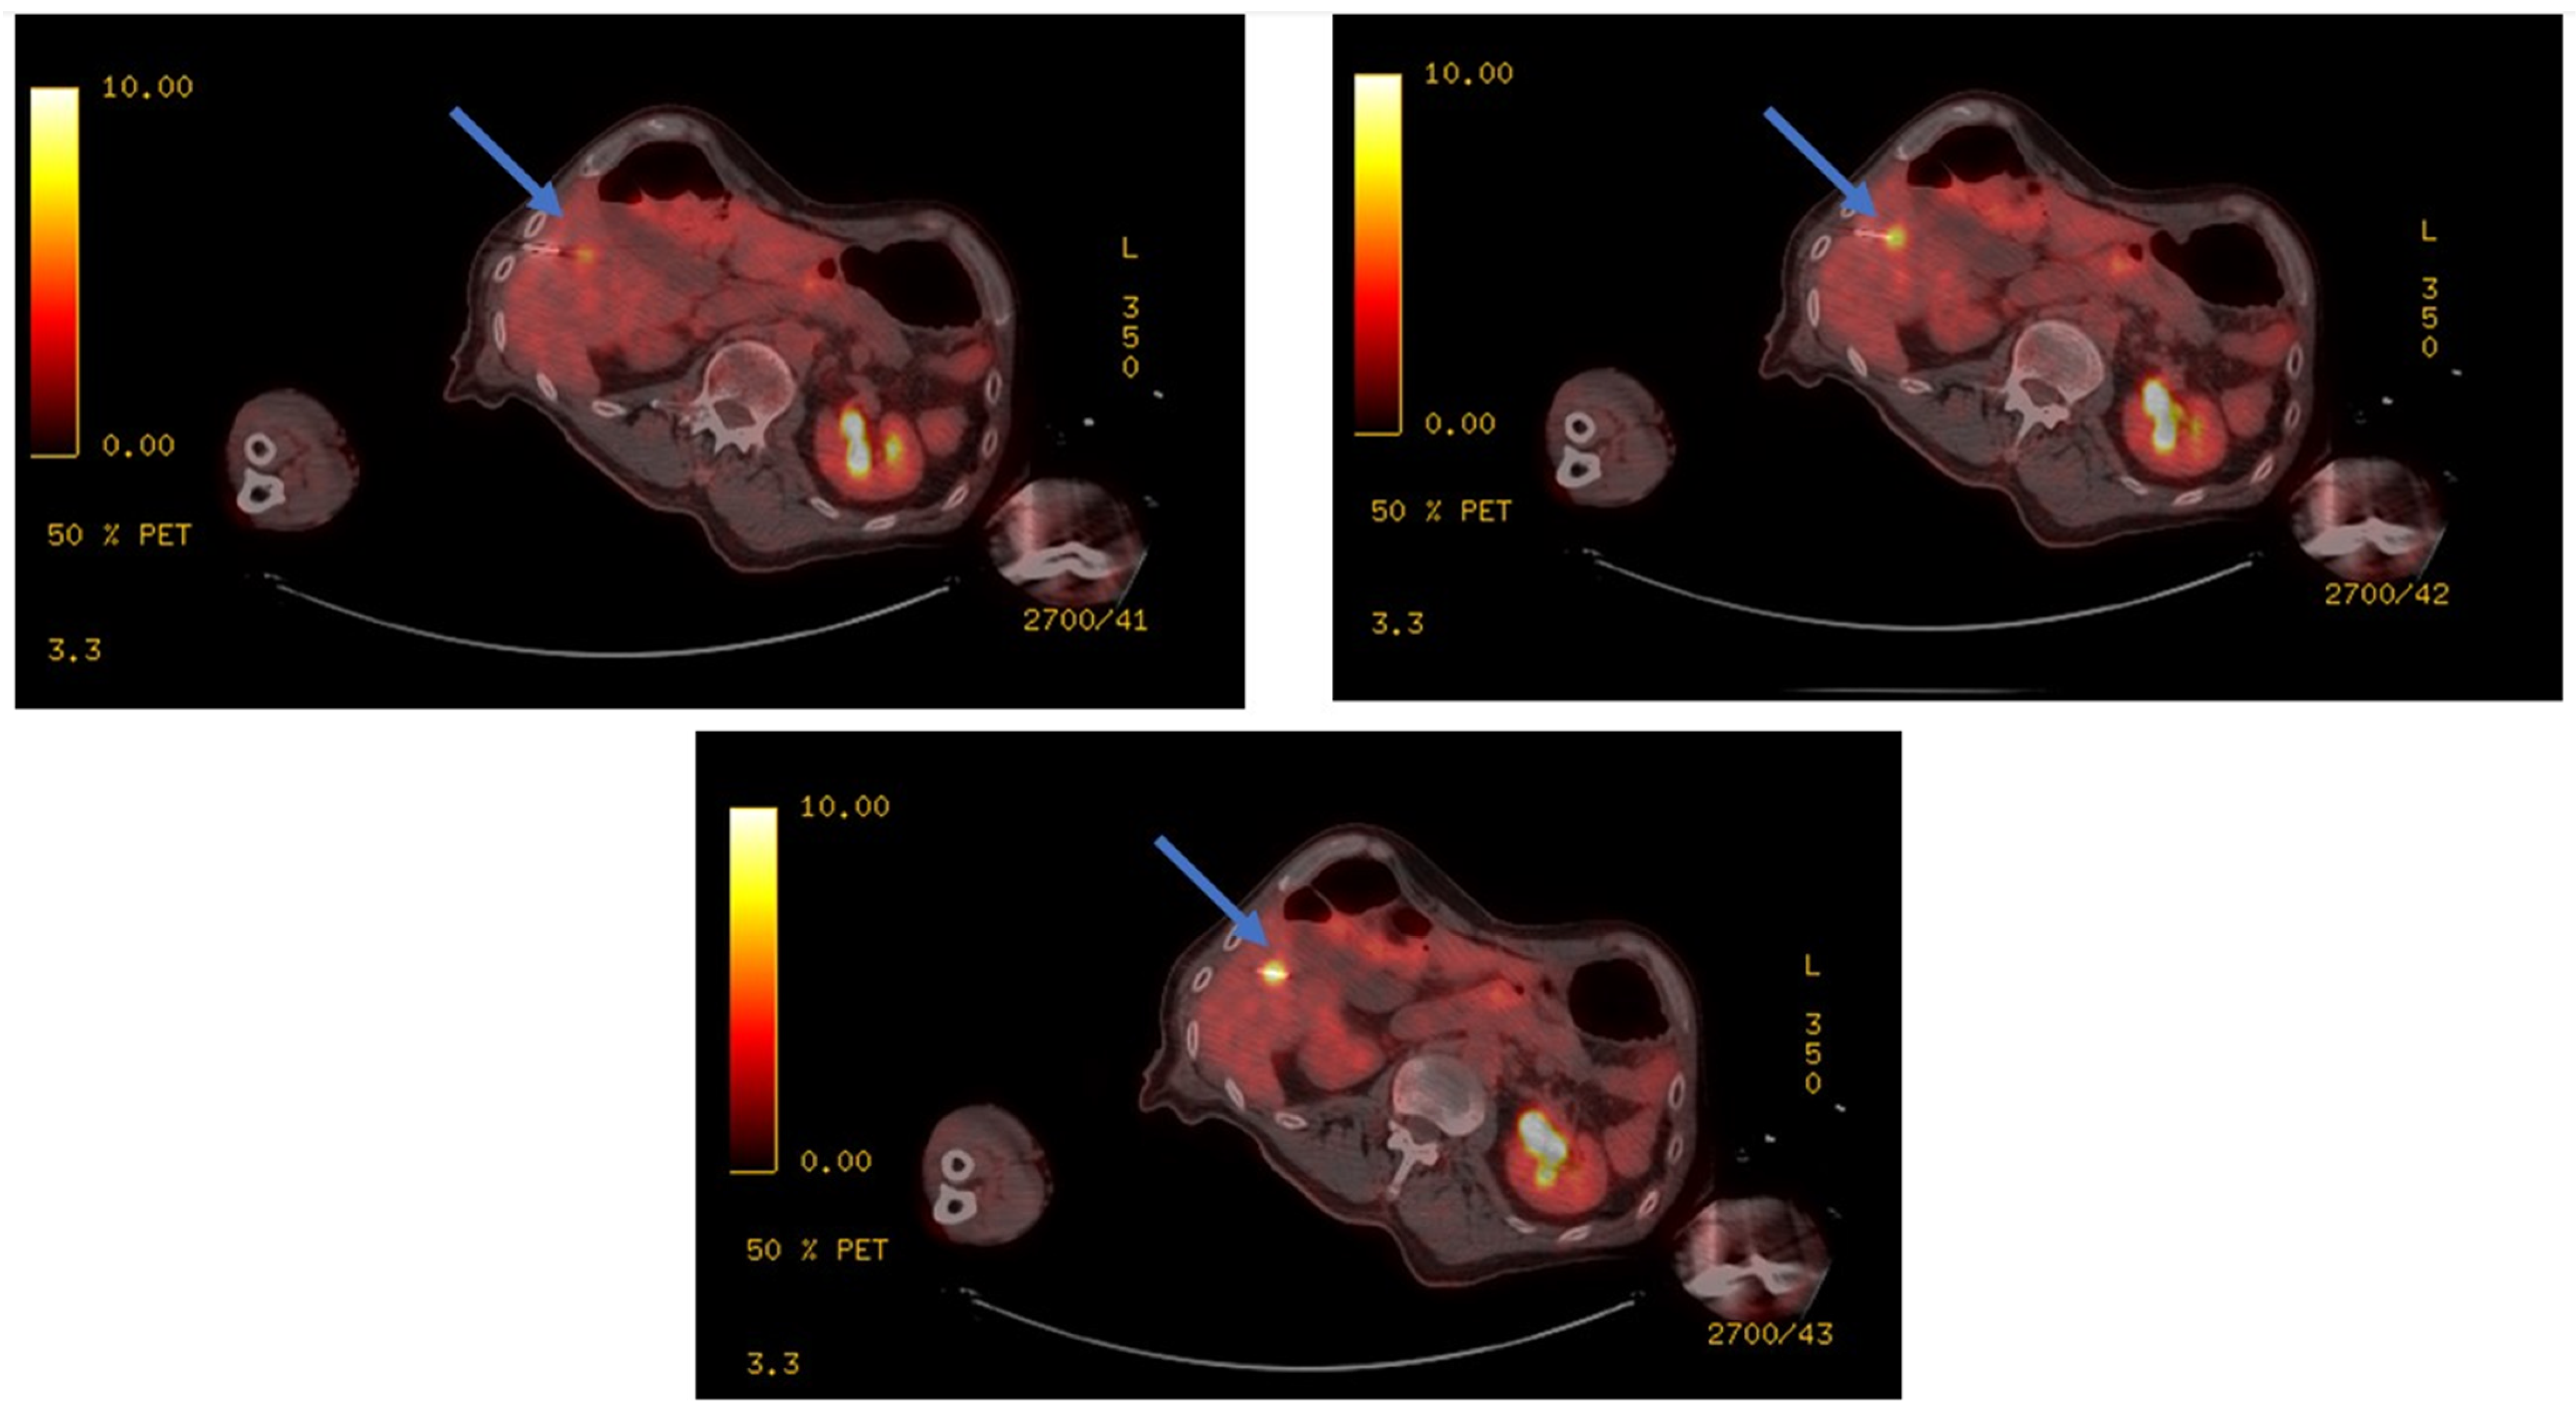

- Ryan, E.R.; Sofocleous, C.T.; Schöder, H.; Carrasquillo, J.A.; Nehmeh, S.; Larson, S.; Thornton, R.; Siegelbaum, R.H.; Erinjeri, J.P.; Solomon, S.B. Split-Dose Technique for FDG PET/CT–guided Percutaneous Ablation: A Method to Facilitate Lesion Targeting and to Provide Immediate Assessment of Treatment Effectiveness. Radiology 2013, 268, 288–295. [Google Scholar] [CrossRef]

- Cornelis, F.H.; Petre, E.N.; Vakiani, E.; Klimstra, D.; Durack, J.C.; Gonen, M.; Osborne, J.; Solomon, S.B.; Sofocleous, C.T. Immediate Postablation 18F-FDG Injection and Corresponding SUV Are Surrogate Biomarkers of Local Tumor Progression After Thermal Ablation of Colorectal Carcinoma Liver Metastases. J. Nucl. Med. 2018, 59, 1360–1365. [Google Scholar] [CrossRef] [PubMed]

- Cornelis, F.; Storchios, V.; Violari, E.; Sofocleous, C.T.; Schoder, H.; Durack, J.C.; Siegelbaum, R.H.; Maybody, M.; Humm, J.; Solomon, S.B. 18F-FDG PET/CT is an Immediate Imaging Biomarker of Treatment Success after Liver Metastasis Ablation. J. Nucl. Med. 2016, 57, 1052–1057. [Google Scholar] [CrossRef] [PubMed]

- Casadaban, L.C.; Catalano, P.J.; Lee, L.K.; Hyun, H.; Tuncali, K.; Gerbaudo, V.H.; Shyn, P.B. Assessing ablation margins of FDG-avid liver tumors during PET/CT-guided thermal ablation procedures: A retrospective study. Eur. J. Nucl. Med. 2021, 48, 2914–2924. [Google Scholar] [CrossRef] [PubMed]